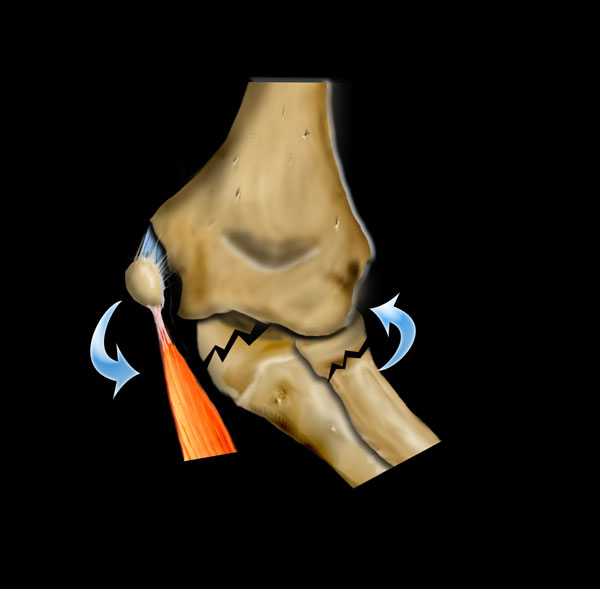

Gãy xương trên lồi cầu được phân loại theo Gartland.

Gãy xương loại I theo Gartland thường khó nhìn thấy trên X-quang do chỉ có di lệch tối thiểu.

Hầu hết các gãy xương này bao gồm gãy xương kiểu cành xanh hoặc gãy xương kiểu vỏ cây.

Dấu hiệu duy nhất gợi ý chẩn đoán có thể là dấu hiệu đệm mỡ dương tính.

Những bệnh nhân này được điều trị bằng bó bột.

Trong gãy xương loại II theo Gartland, có sự di lệch nhưng vỏ xương phía sau vẫn còn nguyên vẹn.

Có thể có một số xoay. Những gãy xương này cần nắn chỉnh kín và một số trường hợp cần cố định xuyên da nếu bột dài cánh tay không giữ được kết quả nắn chỉnh một cách thỏa đáng.

Gãy xương loại III theo Gartland là gãy xương di lệch hoàn toàn và có nguy cơ liền xương lệch và biến chứng thần kinh mạch máu (hình).

Những trường hợp này cần được nắn chỉnh bằng phương pháp kín hoặc nếu cần thiết bằng phương pháp mổ hở. Cố định được duy trì bằng hai đinh bên ngoài hoặc kỹ thuật đinh chéo trong-ngoài.